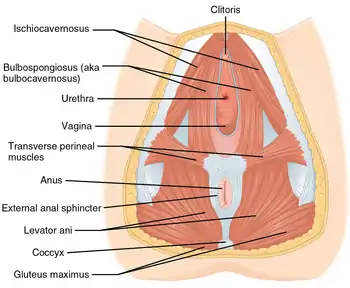

The urethra transports urine from the bladder to the outside of the body. This image shows (a) a female urethra and (b) a male urethra. | |

Female

In the human female, the urethra is about 4 cm long,[8] and exits the body between the clitoris and the vagina, extending from the internal to the external urethral orifice. The meatus is located below the clitoris. It is placed behind the symphysis pubis, embedded in the anterior wall of the vagina, and its direction is obliquely downward and forward; it is slightly curved with the concavity directed forward. The proximal two-thirds of the urethra is lined by transitional epithelial cells, while the distal third is lined by stratified squamous epithelial cells.[12]

Between the superior and inferior fascia of the urogenital diaphragm, the female urethra is surrounded by the urethral sphincter.

Female urethral opening within vulval vestibule Muscles of the female perineum

Muscles of the female perineum Urethra. Deep dissection. Serial cross section.